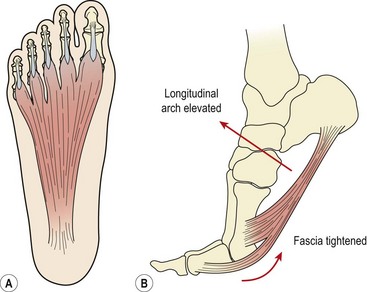

The plantar fascia (plantar aponeurosis) is the thickest fascia in the body. It attaches from a point just behind the medial tubercle of calcaneus and runs anteriorly as five slips. As the slips approach the metatarsal heads, they split into superficial and deep layers (Fig. 12.6A). The superficial layer attaches to superficial fascia beneath the skin, while the deep layer divides into medial and lateral portions to allow the passage of the flexor tendons. Each of the five portions attaches to the base of a proximal phalanx and to the deep transverse ligament.

image

Figure 12.6 Plantar fascia structure and action. (A) Normal tension in fascia. (B) Raising onto the toes tightens the plantar fascia and raises the longitudinal arch.

As the toes dorsiflex and the 1st MP joint is extended prior to toe off, the fascia is wound around the metatarsal head (windlass effect). In so doing the fascia is tightened, shortening the foot and elevating the longitudinal arch (Fig. 12.6B). The combination of these effects supinates the foot and provides a rigid lever for push off. As the foot contacts the ground at heel strike the arch lowers and the foot pronates, becoming a mobile adaptive unit. The plantar fascia is stretched as the foot lengthens.